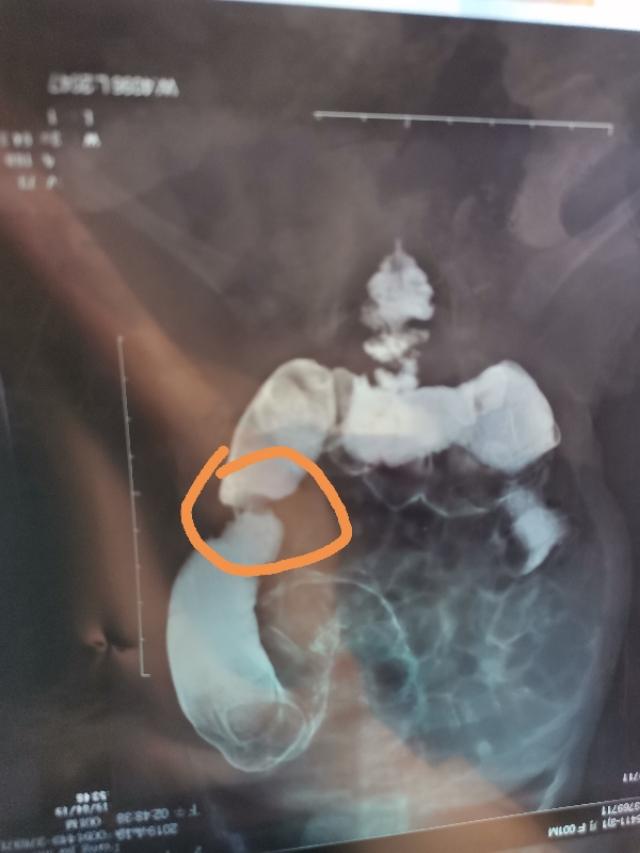

2019年4月17日去儿童医院看医生,医生询问了一些问题,开了甲轴五项,钡灌肠大肠造影、腹部和肠道彩超。甲轴没问题,彩超除了查出腹胀,肠道也因为腹胀看不清。钡灌肠约到第二天和第三天,要做两次才出结果。结果显示降结肠局部肠管狭窄(如图),钡剂排空延迟。我也不太懂,但我知道肯定是有问题,赶紧拿去找医生。消化科医生看到结果又看了片子,大概跟我说了一下,让我直接去新生儿外科。当时的我不明白为什么要让我重新换科,这里看不了吗?后来才知道消化科只看功能性便秘,我们这个属于肠道发育问题,得看外科。